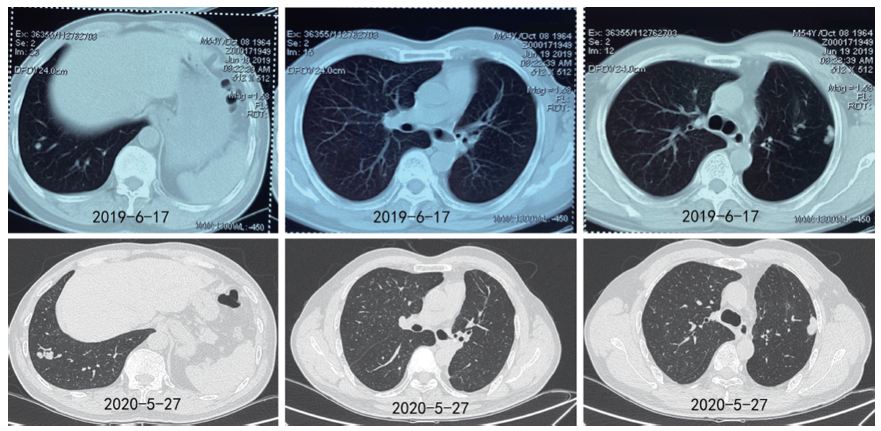

2019-06-17复查CT示左下肺病灶增大, 疗效评价PD, 考虑缓慢进展, 继续口服吉非替尼。2020-05-27行CT示左下肺病灶较前增大, 约2.3 cm(见图4)。

| 图4 吉非替尼治疗中发现左下肺结节逐渐增大Fig.4 Gradual increase in size of left lower lobe nodule during gefitinib exposure |